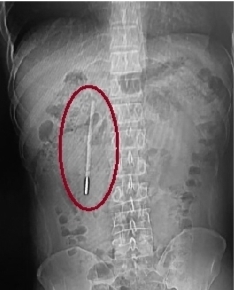

水银体温计“潜伏”肚内20年 随时可能引发肠穿孔大出血

温州网讯 12岁时误吞的一根体温计,竟在肚子里“潜伏”了整整20年。近日,温州医科大学附属第一医院医护团队用内镜从患者王先生的十二指肠处取出体温计。

32岁的王先生最近腹部消化不好,前往温医大附一院龙港院区就诊。该院区医生对其做腹部CT检查,发现其十二指肠处有异物,怀疑是水银体温计,前端已抵在肠壁上,随时可能引发穿孔、大出血等严重后果。追问病史后得知,这根体温计是王先生12岁时不慎误吞的,当时因害怕不敢告知家长,而其身体没出现异样,也就没把这件事放在心上。此次就诊前,他未做过体检。

该院内镜中心医护团队开展内镜下取物操作。由于体温计滞留时间长、位置深,且毗邻胆管胰管,操作空间狭窄,稍有不慎便会损伤肠壁。该团队在相应器械的辅助下精准定位,用圈套器套住体温计一端,缓慢轻柔提拉,经20分钟努力终于将其完整取出,取出的体温计除刻度消失外,外观完好。